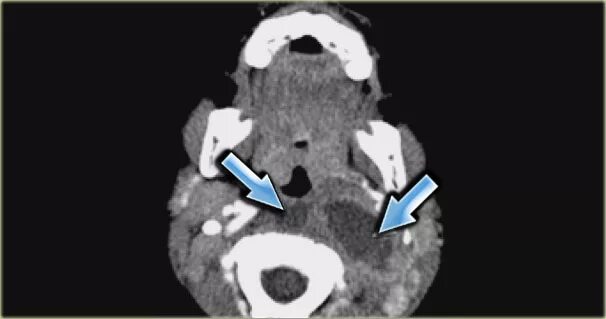

Миндалины на кт